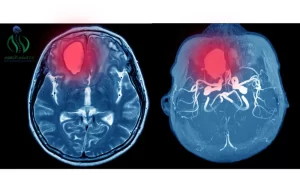

جراحة اورام المخ والأعصاب تعتبر من أعقد الجراحات الحساسة التي تتم , قد يكون ورم الدماغ من نمو خلايا في الدماغ أو بالقرب منها او من أنسجة المخ و تشمل في بعض الأماكن القريبة للأعصاب الغدة النخامية و الأغشية التي تغطي الدماغ . يبدأ تكون أورام داخل الدماغ و هي تسمي الأورام الاوليه , أما الأورام الثانوية فهي تصل من أجزاء أخرى من الجسم إلى الدماغ وتسمى أيضا بالأورام التنقلية.

- التصوير الطبي: يتم إجراء تصوير طبي عن طريق الرنين المغناطيسي أو التصوير المقطعي بالأشعة المقطعية , حيث يتم تقديم صور ثلاثية الأبعاد للمخ والأعصاب لتحديد نوع الورم و خصائصه.